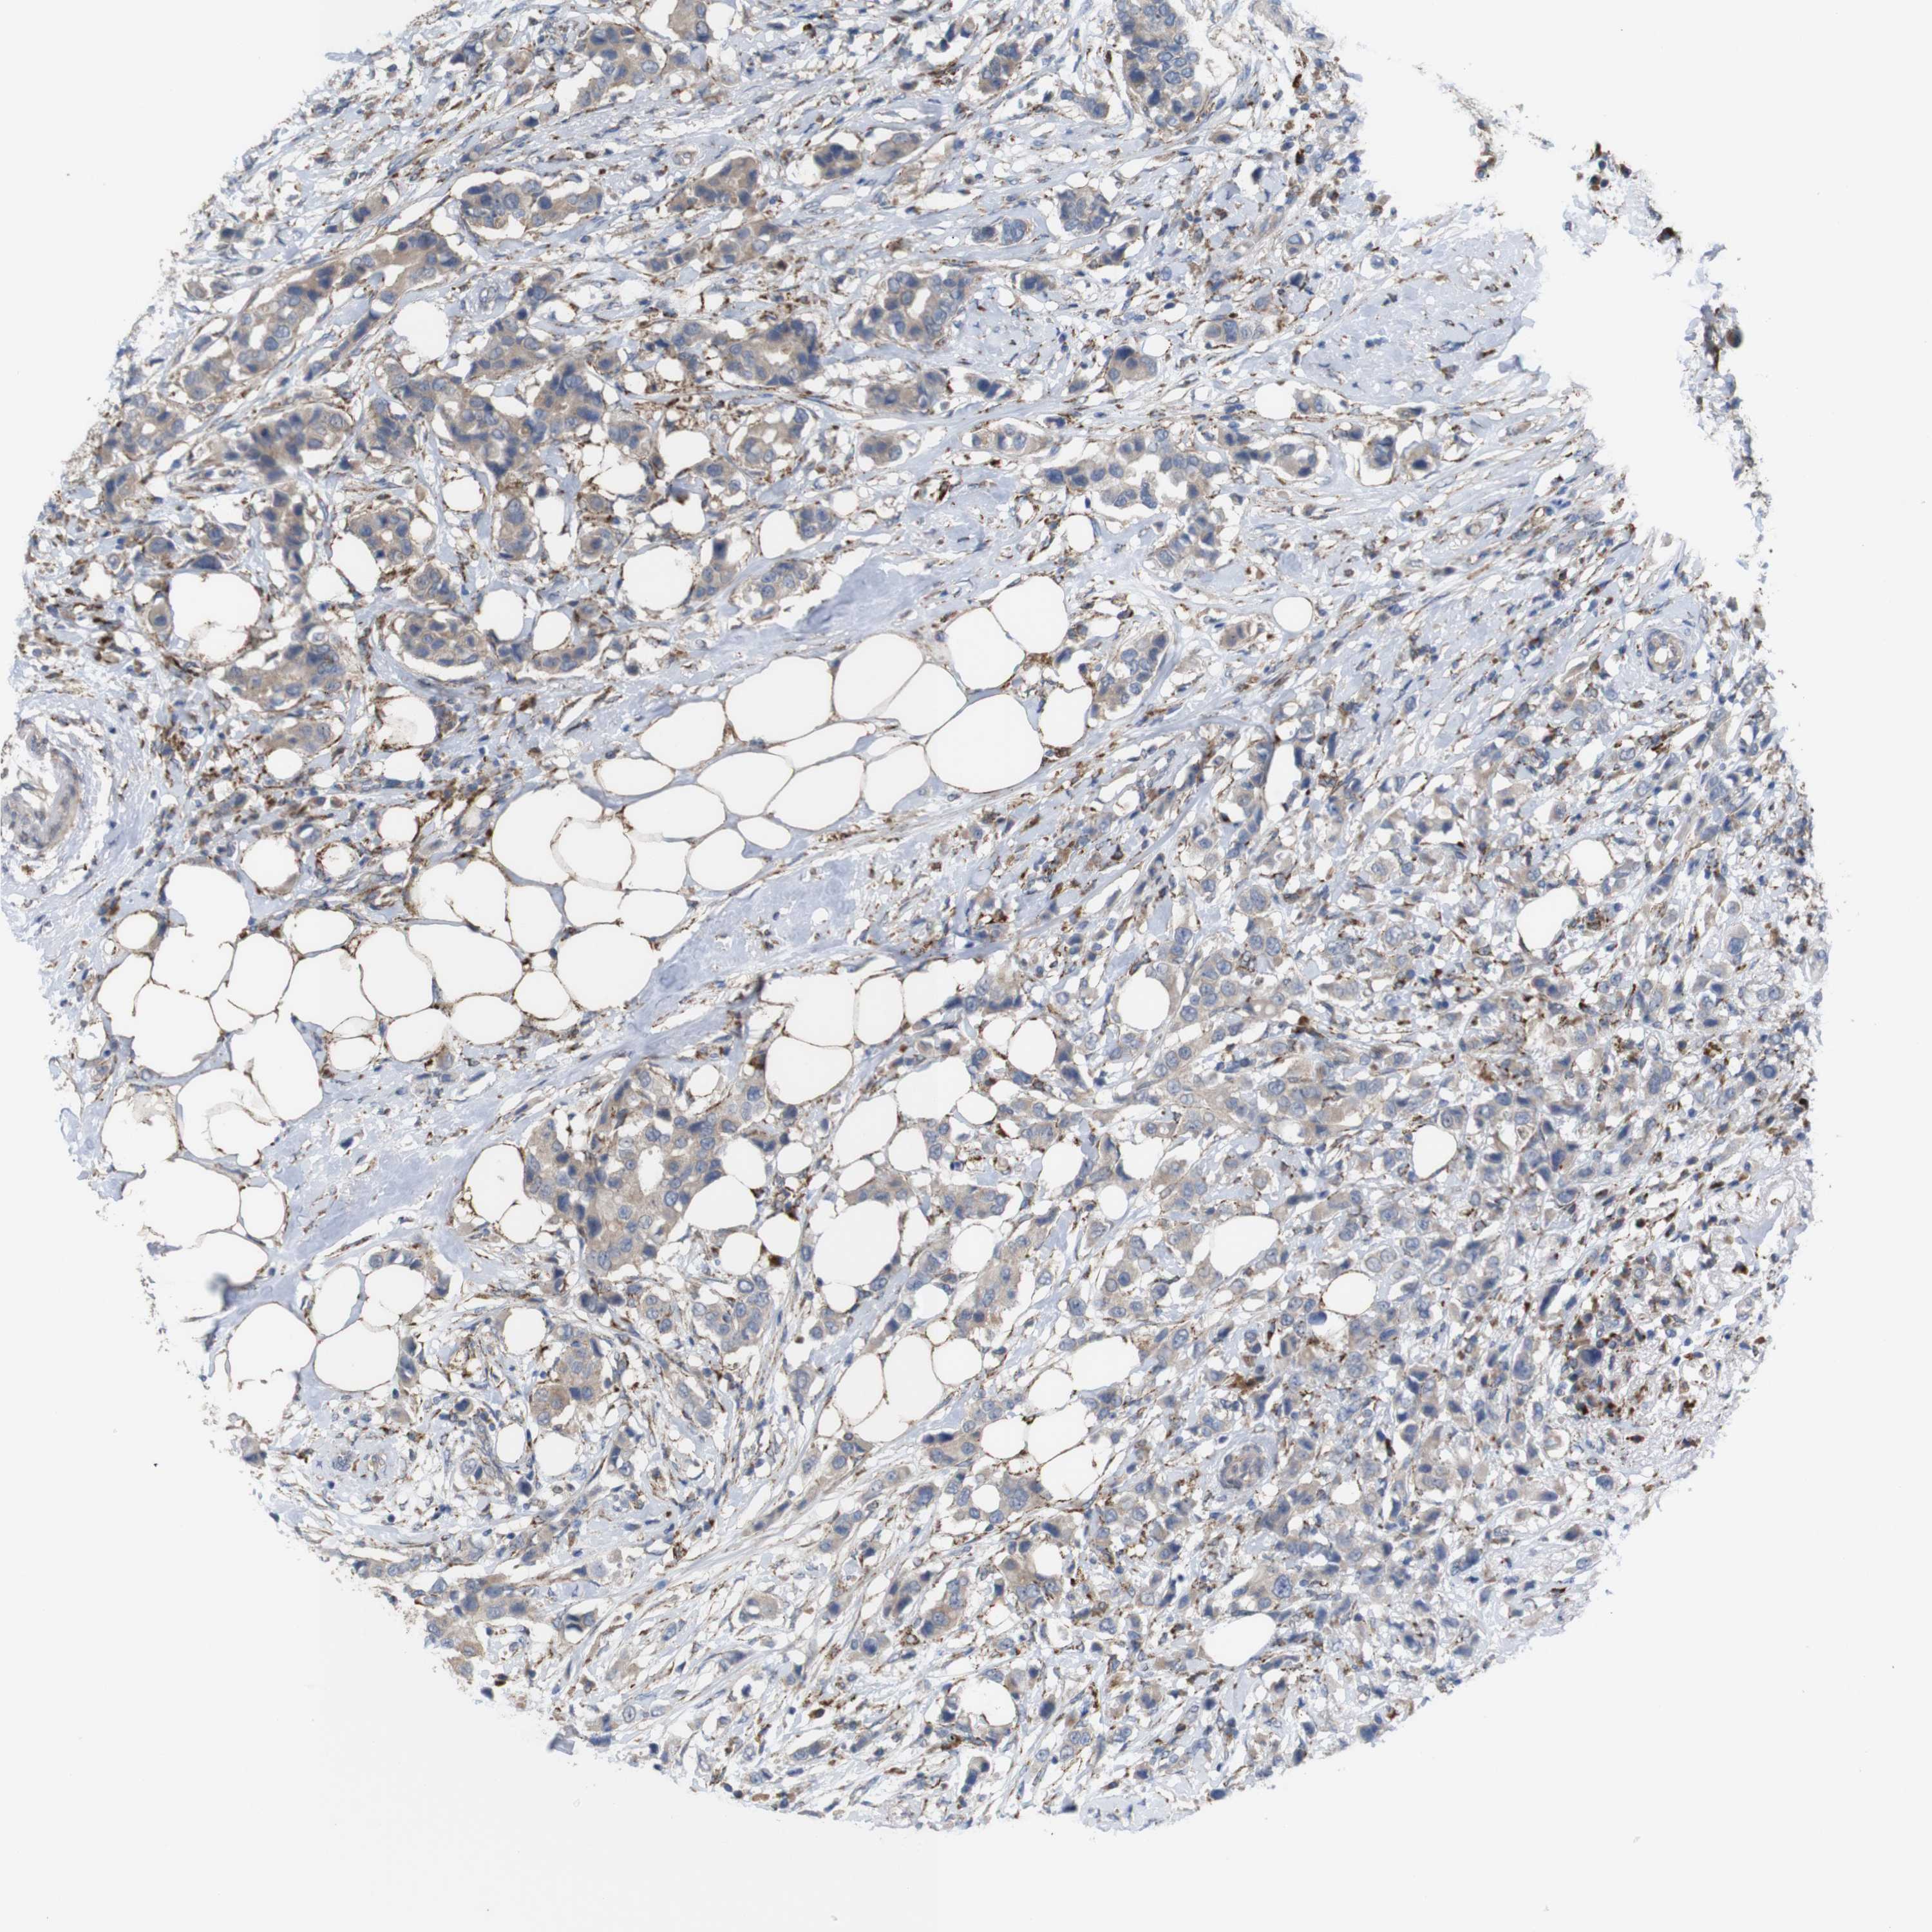

CANCER BREAST CANCER Show tissue menu

BRCA TCGA BRCA VALIDATION PROTEIN EXPRESSION